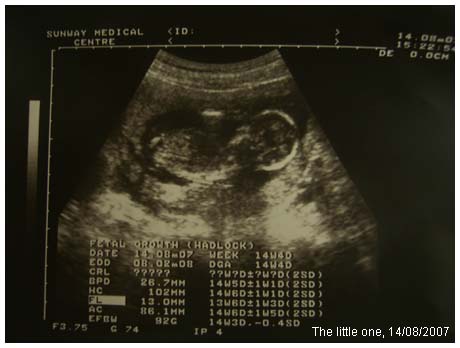

小北鼻有長大﹐已經不用醫生說﹐我都看得出那裡是頭﹐那裡是腳和手了。

(寶寶照片沒有在身邊﹐晚些才放上來)